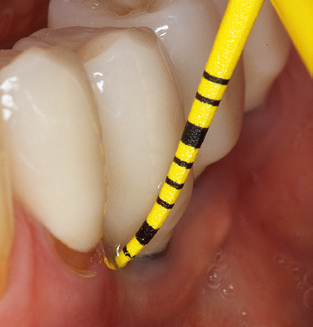

Updating the patient’s medical history is an important aspect of SPT and should occur at least once per year. It helps the dental team to identify and document any new risk factors. Especially when a patient is treated over many years, it is important to establish whether patient-specific and general health risk factors have changed. This primarily concerns a heightened risk as a result of diabetes, but other general conditions (cardiovascular disease and neoplasia) can also produce a modified risk profile as a result of the treatment performed and medication administered. Accordingly, updating the medical history as part of SPT is very important, as a modified risk profile may trigger the need to adapt the treatment interval. In the next step, it is important to afford the diagnostics due attention. Whilst instruments are a central aspect of SPT, findings and their documentation must never be neglected. The periodontological findings are essential for a good diagnosis; increases in the pocket depths and the BOP index are clear indicators of advancing periodontal and peri-implant disease. As such, the team should not shy away from probing implants too, with the aim of gathering the requisite data. At the same time, it is important to use periodontal probes with millimetre markings. Metallic probes have already been used for determining pocket depths around natural teeth for decades. In the case of implants, the challenge of recording correct and reproducible pockets depths is even greater. As the discrepancy between the implant diameter and the contour of the superstructure regularly results in overcontouring of the superstructure, flexible probes which still feature millimetre markings are a sensible solution for measuring pocket depths around implants (e.g., Colorvue Kit PCV11KIT6, Hu­Friedy; Fig. 4).

Fig. 4: Flexible probes with millimetre markings are recommended for the probing of dental implants (e.g. Colorvue Kit PCV11KIT6, Hu­Friedy). – Fig. 5a and b: A straight working tip (1P, W&H Dentalwerk Bürmoos GmbH) is a suitable instrument for use on all natural teeth. – Fig. 6: Curved working tips (3Pr/3Pl, W&H Dentalwerk Bürmoos GmbH) lend themselves to the processing of difficult-to-reach areas of the tooth and root surfaces (e.g. furcations). – Fig. 7: The tapered, hexagonal implant cleaning tip (1I, W&H Dentalwerk Bürmoos GmbH) permits atraumatic and efficient cleaning of the crown and abutment surfaces. – Fig. 8: Titanium and carbon curettes are suitable instruments for the manual cleaning of the implant surfaces.